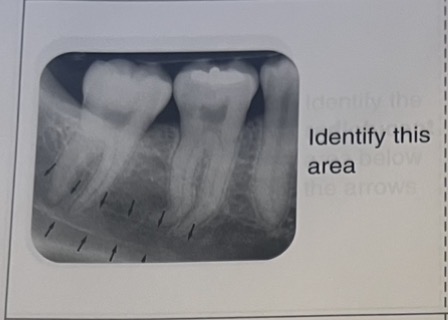

Mandibular canal

External oblique ridge

Internal oblique ridge

Submandibular fossa